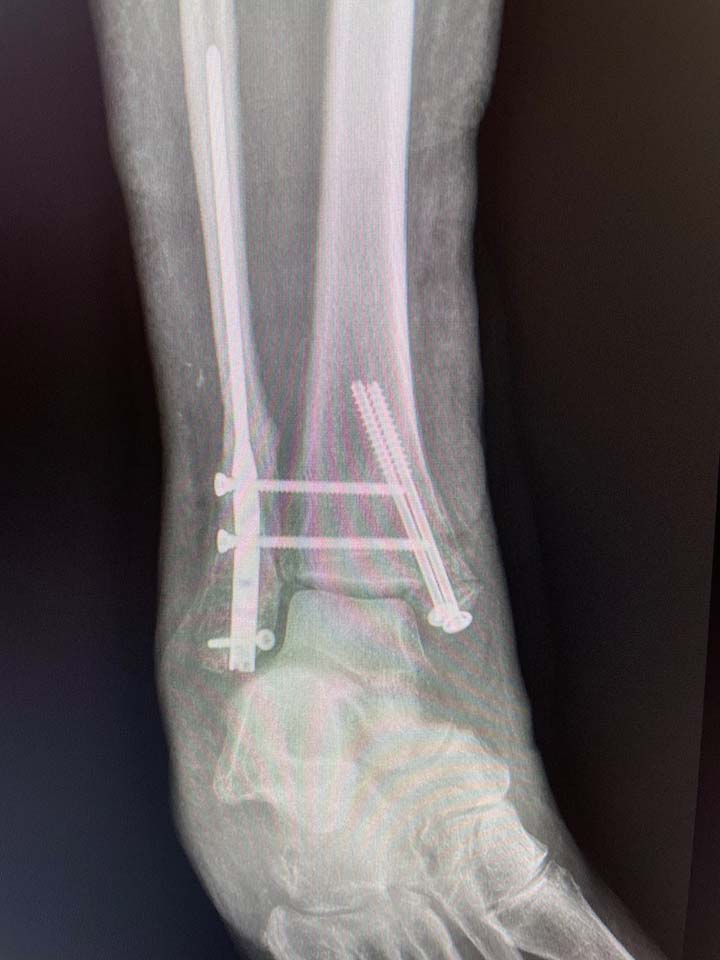

In contrast to traditional ORIF of the ankle, Fibunail is inserted in the distal fibula through a minimal stab incision.

Once the nail is implanted, screws are inserted through a precision targeting device by making stab incisions to protect the soft tissue envelope and preserve vascularity of the periosteum.

The Fibunail features a radiolucent targeting guide which aids in the anatomic placement of both A/P and M/L screws and allows for syndesmotic screw fixation, all through minimally invasive stab incisions.